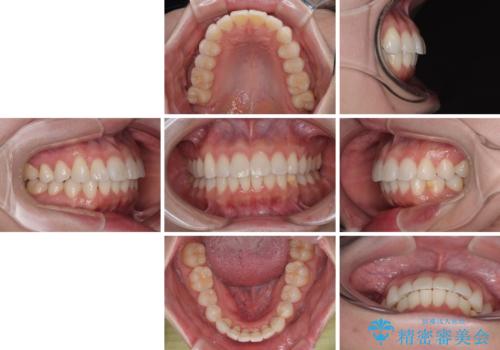

- インビザライン・モデレート

- 11ヶ月

- 2-5回

インビザライン・モデレートは、製作できるアライナーの枚数に制限があるため、移動可能な量に限りがあるものの、インビザライン・ライトよりも枚数が多いため、幅広い症例に対応可能です。